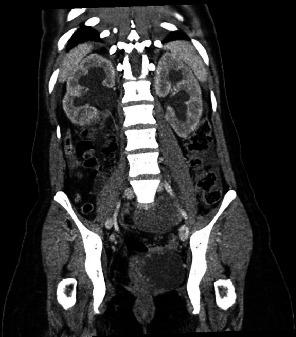

子宫内膜异位症是育龄妇女常见的妇科疾病,其症状多种多样,如盆腔疼痛、月经过多、痛经、排便困难和不孕。子宫内膜异位症是子宫内膜异位症的一种,其特征是囊性肿块,最常见于卵巢。本病例讨论的是一个罕见的 25 厘米子宫内膜异位症患者的治疗方法,该患者之前未确诊为子宫内膜异位症,因急性高血压急诊入院。据认为,巨大的囊肿对肾脏血管造成了肿块效应,引发了新血管性高血压,需要立即进行干预。该病例采用微创手术切除囊肿并溶解粘连,术后未出现并发症。

Endometriosis is a common gynecological condition in women of reproductive age and has variable symptomology such as pelvic pain, menorrhagia, dysmenorrhea, dyspareunia, and infertility. Endometriomas are a form of endometriosis and are characterized by cystic masses most commonly found on the ovaries. This case discusses the management of a rare occurrence of a 25-cm endometrioma in a patient without a prior diagnosis of endometriosis, who presented to the emergency room in an acute hypertensive emergency. It is believed that the large cyst caused a mass effect against renal vasculature precipitating renovascular hypertension that required immediate intervention. This case was approached with minimally invasive surgical removal of the cyst and lysis of adhesions without postoperative complications.